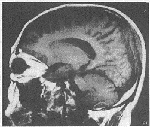

患者男,62岁。咳嗽胸痛,左锁骨上淋巴结肿大10天入院。查体:双侧锁骨上淋巴结肿大,右肺呼吸音低,心率102bpm。胸片:右下肺巨大肿块影,可见分叶、毛刺且与胸膜粘连。纤支镜检查仅见右肺上叶及舌叶支气管分嵴增宽。心脏彩超示心包积液。左锁骨上淋巴结活检的病理诊断:转移性低分化鳞癌。行MVP方案一疗程,咳嗽胸痛症状消失,肿大淋巴结回缩,复查胸片右肺肿块缩小2/5。但出现轻度恶心,头晕症状。行头颅CT检查未见异常,故出院。15天后因头痛恶心呕吐再次入院。查体发现颅顶部局限性隆起,范围约1.5cm×2cm,质硬。头颅MR:平扫:后顶枕部可见不规则肿块影,轴位大小约3cm×4.9cm。T1WI呈低信号,T2WI呈高信号。矢状位T1WI:可见肿块沿脑膜及颅骨生长,长8cm,并侵入蛛网膜下腔。硬脑膜明显增厚,脂肪板障高信号消失,内、外板骨质破坏,并侵入皮下(图1)。+C:脑膜及肿块可见不均匀增强(图2)。

图1 SE T1W矢状位:后顶枕部不规则肿块影,肿瘤侵及蛛网膜下腔、硬脑膜、颅骨内外板

及板障

讨论 颅骨转移瘤临床较少见,主 要来源于肺癌、乳腺癌、前列腺癌。其转移途径主要是血行转移。骨转移的影像学表现一般分为:①溶骨型。②成骨型。③混合型及囊状扩张型。本例表现以溶骨型改变为主。病灶不但侵犯颅骨而且沿脑膜扩展,使脑膜增厚,并穿过硬脑膜,侵入蛛网膜下腔。属于脑膜转移瘤亦可属于颅骨转移瘤,至于首先转移至 脑膜还是颅骨有待进一步研究。由于颅骨在MR像上显示为无信号,所以当颅骨病灶不甚明显而仅有颅内病灶时,易被误诊为恶性脑膜瘤。矢状位对显示蛛网膜下腔、硬脑膜、颅骨内、外板及板障的层次很有帮助。此外,对有临床症状的患者,虽头颅CT未见异常,亦不能轻易排除脑膜转移,应进一步行MR检查以确诊。